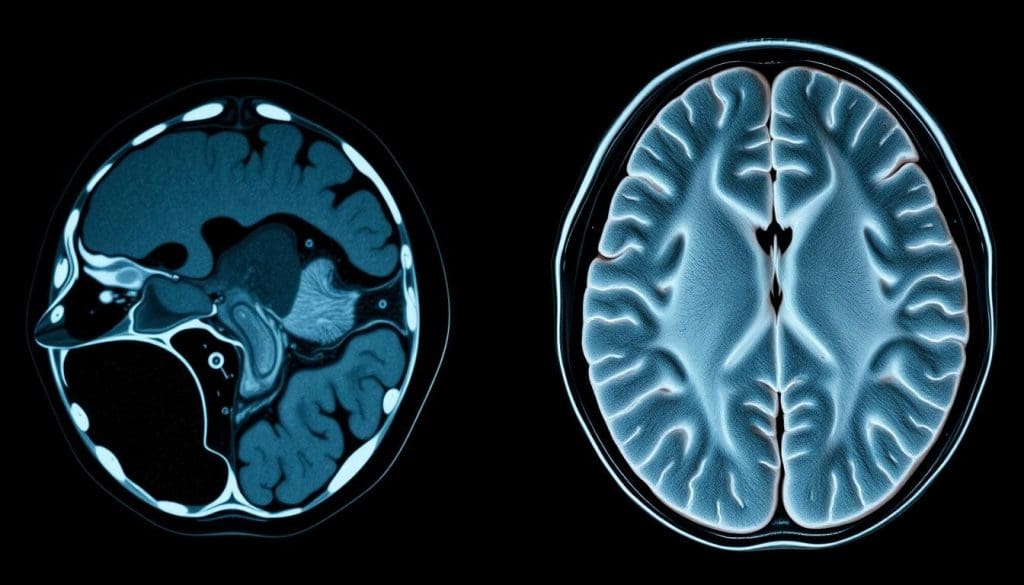

When MRI Is Superior for Brain Assessment

Detailed Soft Tissue Evaluation

MRI shines because it gives a detailed look at soft tissues. Unlike CT scans, MRI can tell soft tissues apart, showing brain anatomy and problems clearly. This helps a lot in finding diseases that affect the brain’s soft parts.

- High-resolution imaging of brain structures

- Ability to detect lesions and abnormalities in soft tissues

- Enhanced visualization of cranial nerves and their pathology

Detecting Subtle Brain Abnormalities

MRI is great at catching small changes in brain tissue that CT scans might miss. It’s perfect for finding early signs of diseases, infections, and other issues that need quick action.

- Early detection of multiple sclerosis lesions

- Identification of small tumors or cysts

- Visualization of periventricular white matter changes

Visualizing White and Gray Matter Pathology

MRI can tell white and gray matter apart, which is key for diagnosing and tracking diseases. This is important for conditions like Alzheimer’s and multiple sclerosis.

MRI gives a full view of brain anatomy and problems, helping doctors make better diagnoses and treatment plans. Its skill in soft tissue, spotting small issues, and showing white and gray matter makes MRI essential for brain checks.